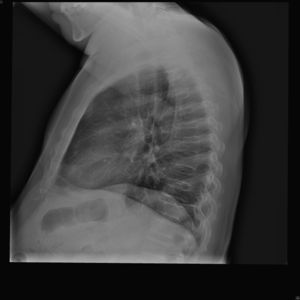

Caso clínicoVarón de 59 años con antecedente personal de diabetes mellitus tipo 2 en tratamiento con antidiabéticos orales, que acude a consulta de Reumatología por dolor inguinal bilateral y dorsolumbalgia de intensidad dolorosa progresiva, ambos de ritmo mecánico, que el paciente califica de muy intenso y que desencadenan dificultad progresiva para la deambulación; y por episodios de disnea de moderados esfuerzos, cuyo origen, estudiado por Neumología, era debido a dificultades en la expansión torácica. El cuadro doloroso no había presentado una respuesta satisfactoria a antiinflamatorios no esteroideos ni a opiáceos menores. En la exploración física se observa talla de 146cm, marcada cifosis dorsal, obesidad troncular, limitación importante para la flexoextensión y las rotaciones de ambas articulaciones coxofemorales, y braquidactilia en ambas manos. Hemograma y bioquímica sanguínea con valores normales. El estudio radiológico convencional de columna dorsolumbar, anteroposterior de pelvis y posteroanterior de manos se muestran en las figuras 1 a 4.

El paciente descrito presenta datos que sugieren una displasia espondiloepifisiaria tarda. Esta entidad tiene una herencia recesiva ligada al cromosoma X1, estando por lo tanto afectados sólo los varones. Se han descrito mutaciones en el gen SELD en el cromosoma Xp22.12-p 23.311. El diagnóstico se realiza entre los 5 y los 10 años de edad, cursando con enanismo de tronco corto; esto es, retraso en el crecimiento de la columna vertebral con una talla media final de 145cm y desproporción entre la longitud de las extremidades y el tronco2,3. La articulación coxofemoral está siempre afectada en coxa vara con aplanamiento leve de las epífisis, que conducen a cambios artrósicos precoces, y que pueden, en estadios más avanzados, incapacitar al paciente2–4. A nivel axial se describen cambios displásicos vertebrales con platiespondilia, que provocan cifosis progresiva4–6 con aumento del diámetro anteroposterior del tórax, y que en último término puede provocar episodios de disnea. No aparece retraso mental, se han descrito formas familiares con asociación a condrocalcinosis7,8 y existe una forma de displasia espondiloepifisiaria tarda asociada a artropatía degenerativa precoz, que puede simular artritis reumatoide juvenil9.